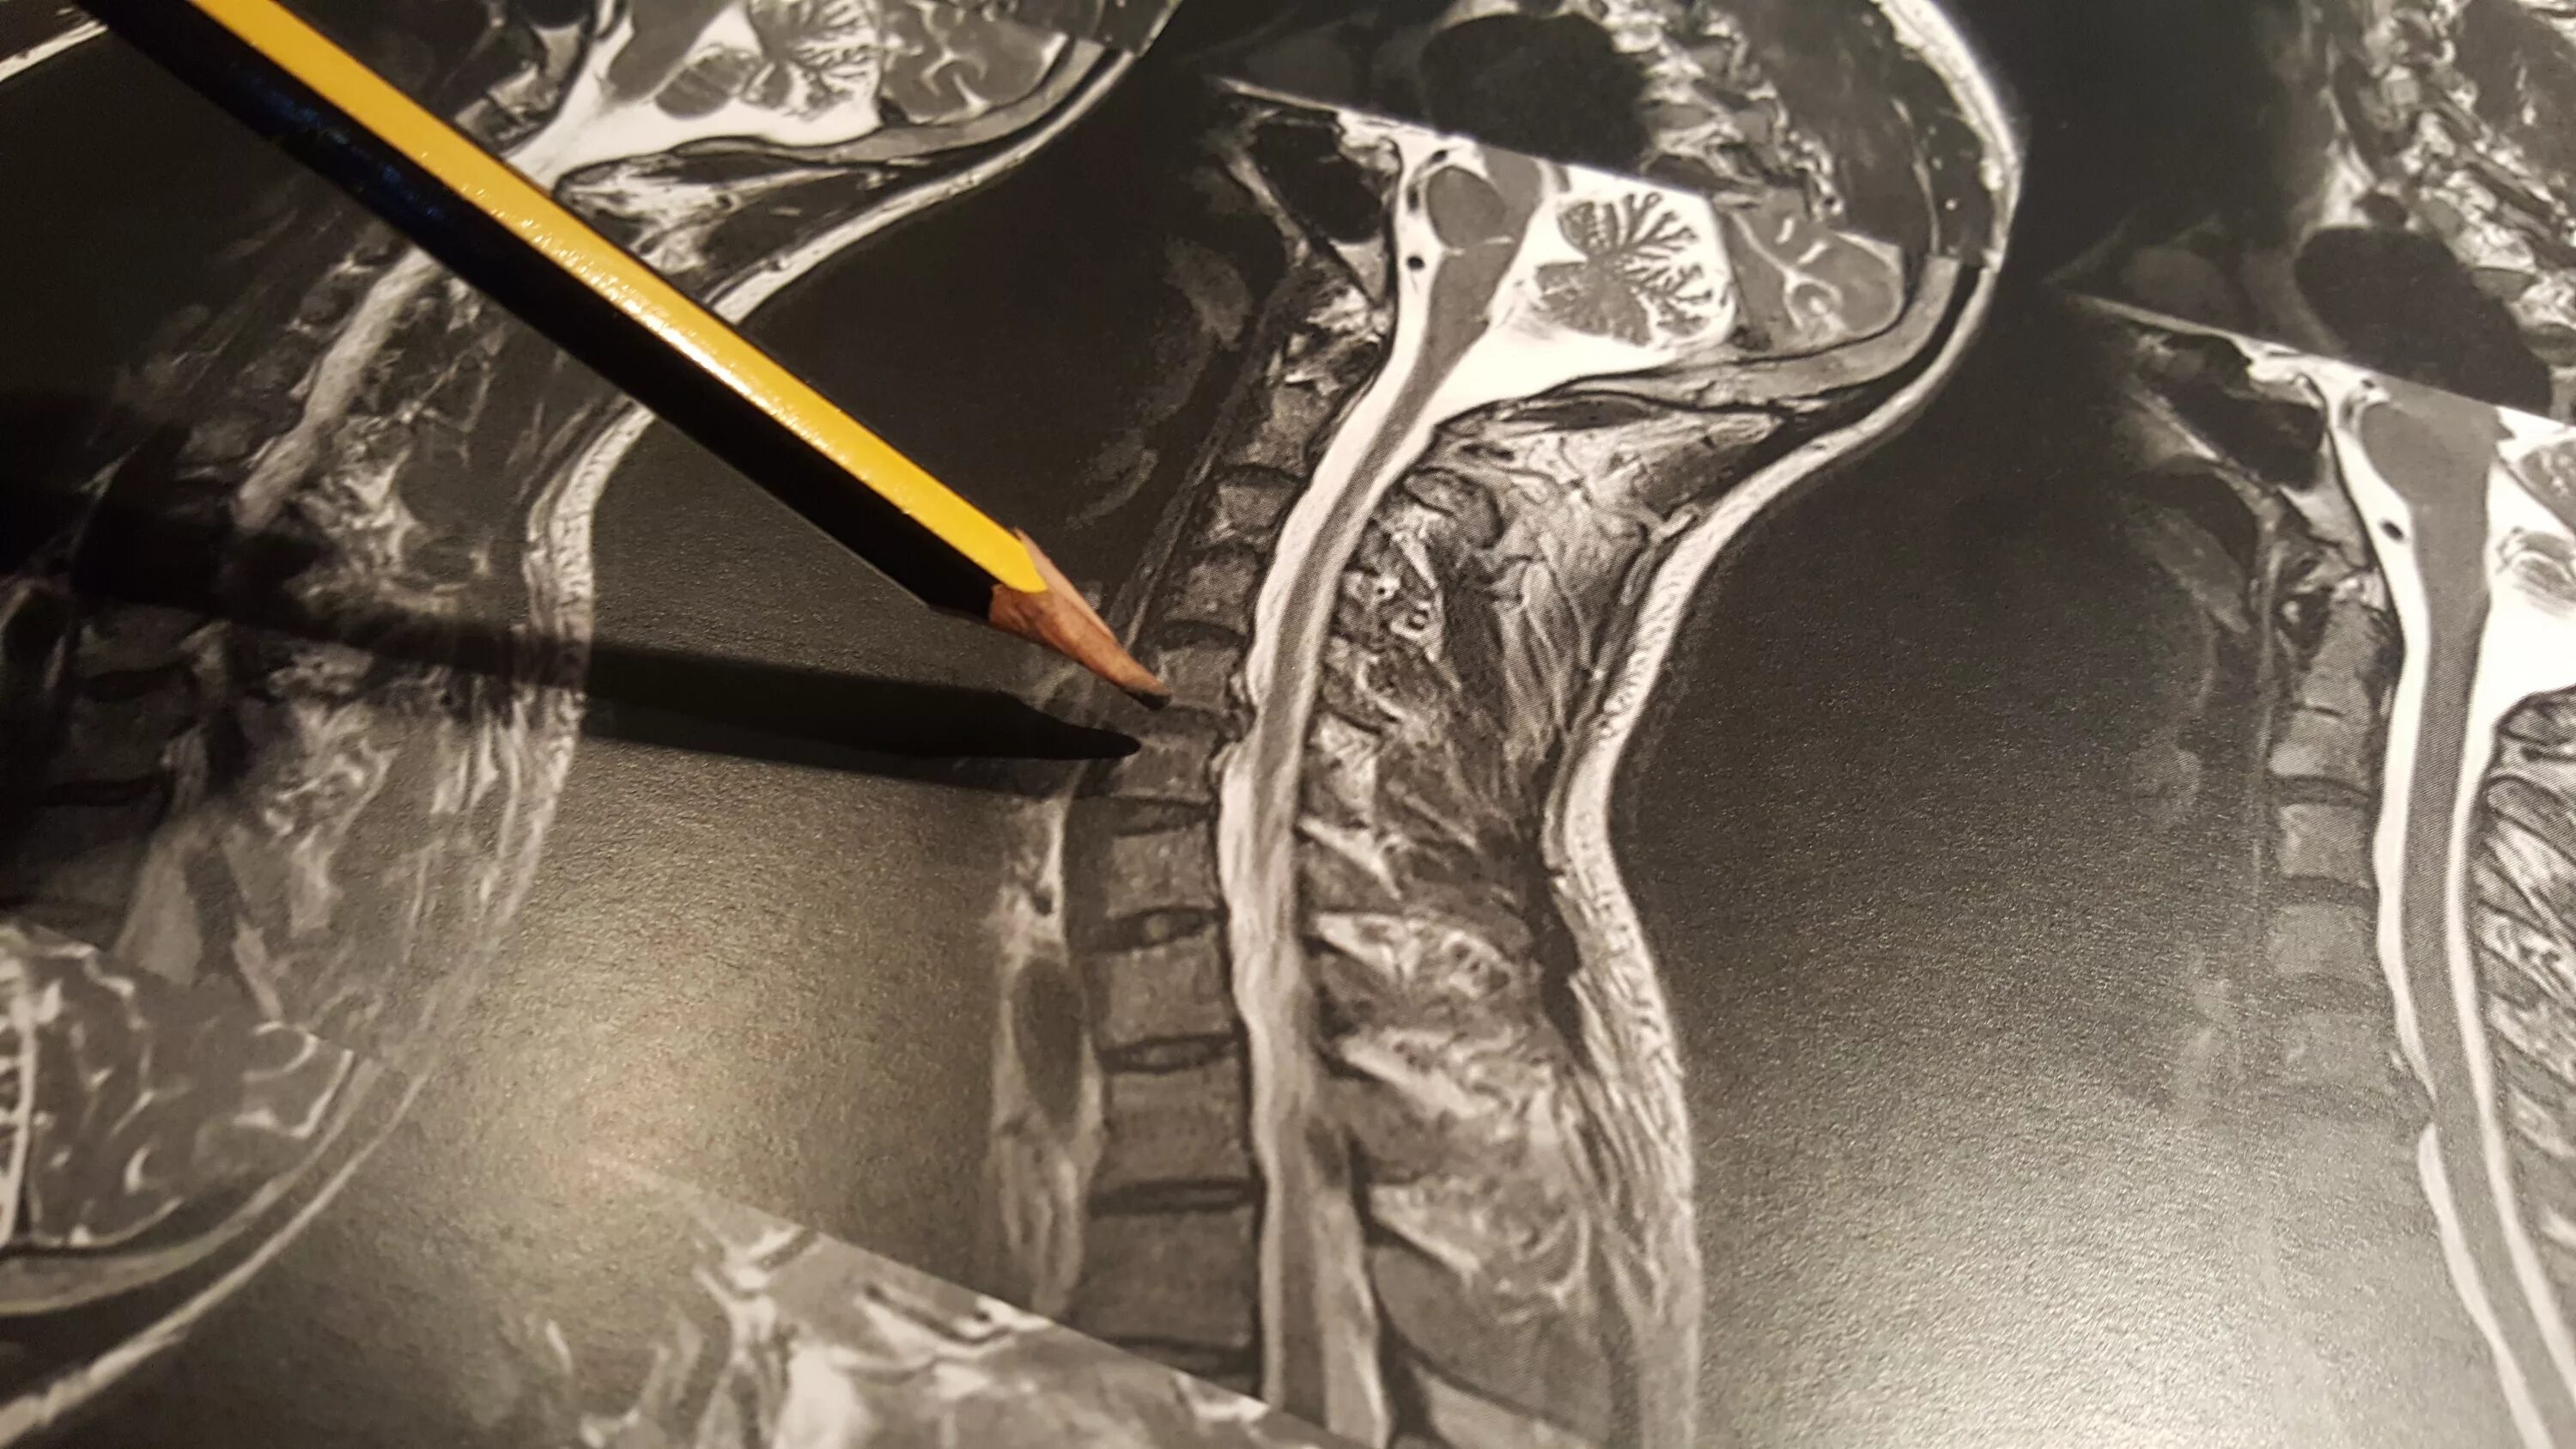

Грыжа шейного мкб